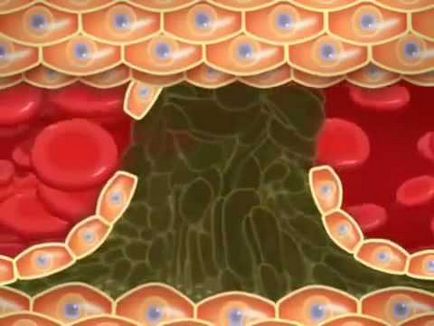

Érelmeszesedést. Alapvetően ez a betegség befolyásolja az artériák minden méretben, ami a kialakulásához is. Koszorúér ateroszklerózis kialakulásához vezet a szívkoszorúér-betegség. Győzd cerebrovascularis - encephalopathia, vagy a fejlődés a ischaemiás stroke.

Visszér. Ez hatással van a vénás rendszer a személy. A betegség oka a gyengeség a érfalak a vénák, és patológiája a szisztémás keringésbe, ami megnövekedett nyomás a vénás rendszerben.

A patológia vaszkuláris rendellenességek lágy szövetek jelzik a tápellátást, amely megnyilvánult sápadtság, olykor kékes, Bíbor szöveti helyre, vagy végtagokban (általában lábakban), érzés zsibbadás vagy bizsergés, hűtés a bőr területen (általában kezdődik a lábujjak).

Vizuális módosítása hajók a bőr, visszértágulat az alsó lábszár és a láb, a vaszkuláris pályák jelezheti mind krónikus, mind akut vaszkuláris betegségek (thrombophlebitis, lymphangitis, és így tovább. D.).